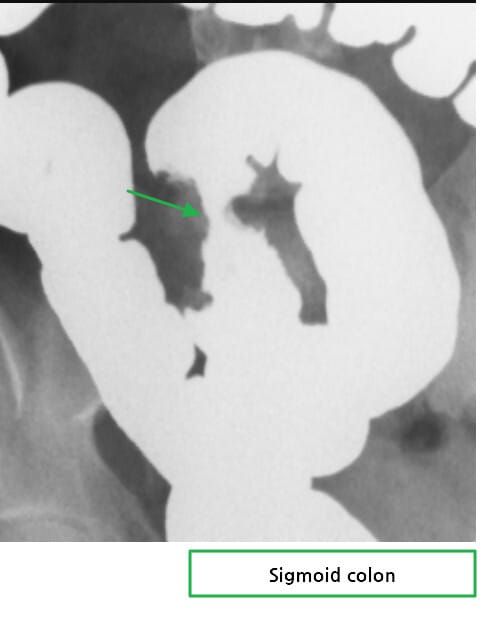

바륨관장(Barium enema) 소견

🔴 Apple core sign (사과껍질 징후)

중앙이 좁아진 고리 형태의 협착으로, 전형적인 결장암 소견입니다.

🔴 Shoulderring sign

병변 양쪽 경계가 불규칙하게 어깨처럼 돌출되어 보이며, 암의 침윤을 시사합니다.

Abdrabou A, Carcinoma of sigmoid colon. Case study, Radiopaedia.org (Accessed on 15 Jul 2025) https://doi.org/10.53347/rID-23071